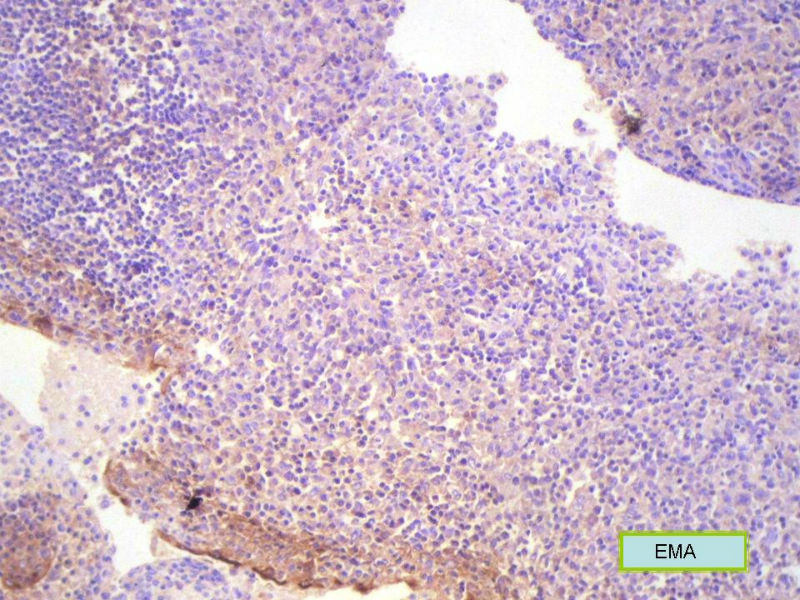

该患者可能存在病毒的感染,抑或是EB病毒的感染,包括CD30+的细胞在内,夹杂在组织细胞、小淋巴细胞之间的一些个大细胞是活化的淋巴细胞,表型看来属B细胞。整个形态呈反应性增生的形态。

请看下图,显示的细胞比较杂,胞浆较丰富,胞核没有什么特别的异型性。没有促纤维增生反应和围血管生长表现,没有肿瘤性坏死,没有见到更多的核分裂,特别是病理性核分裂。因此认为,本例是淋巴组织反应性增生,可能是对病毒感染的反应。